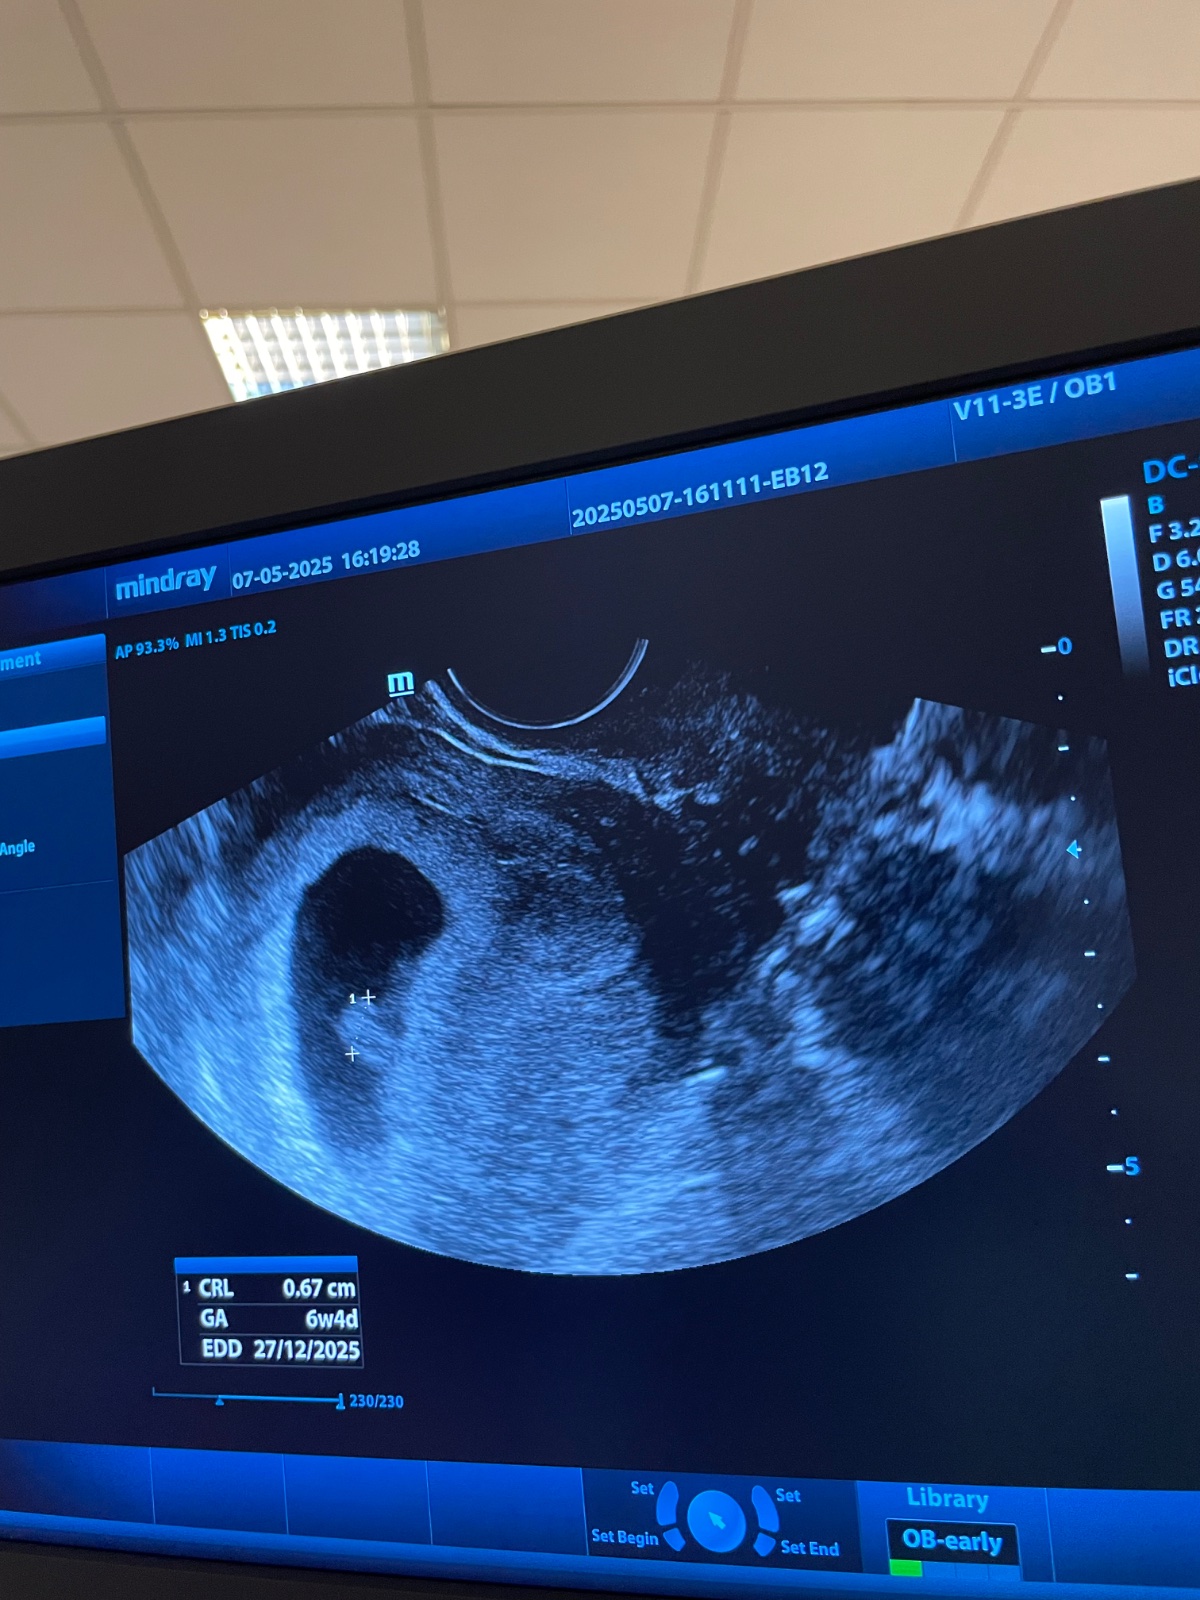

Na sone bol vidieť iba gestacny a zltkovy vak bez embrya - 8,5mm v 5tt +5dni..a nakoniec to dobre dopadlo?

je to 50/50... v tom tydzni som mala bodku v gestacnom vaku.. ale vedeli sme presne kedy bola ovu... aj sex... hlavu hore... uz je to len v bozich rukach...